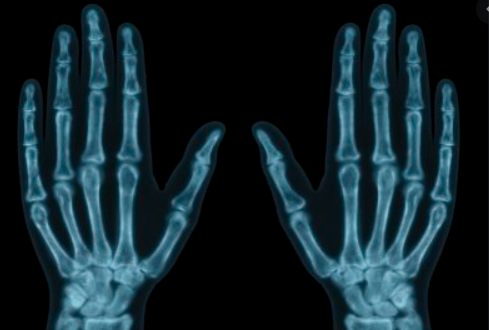

전리방사선 및 비전리방사선의 취급과 방사성동위원소를 이용한 행의학검사와 초음파검사 등 관리 및 취급 업무를 하는 사람을 말합니다. 보통 병원에 가서 엑스레이 검사를 하거나, CT, MRI 검사를 하는 사람들이 방사선사이고, 핵의학과, 방사선종양학과에서 일하는 사람도 방사선사입니다.